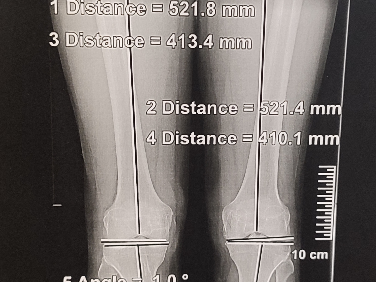

La planification préopératoire de cette intervention est essentielle car la principale cause d’échec est la non-correction ou l’hyper-correction de la déformation initiale. Il faut aussi repérer l’origine de cette déformation (tibiale ou fémorale) pour guider le geste chirurgical.

En complément de l’analyse radiographique, de grandes avancées technologiques ont émergé ces dernières années pour permettre de planifier sereinement cette chirurgie (Navigation assistée par ordinateur, guides de coupe imprimés par des imprimantes 3D).